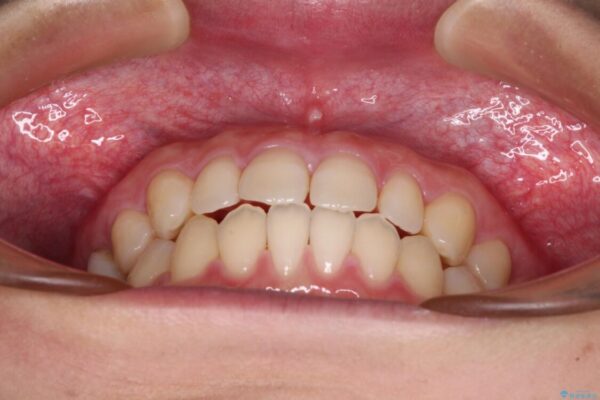

治療前

• 隙間だらけの歯列 インビザラインで改善 治療前画像

前歯の上下スペースと前歯の隙間を気にして来院された患者様です。

飲み込みや話をするときに舌を突出させる癖が強くあり、それが原因でスペースが空いていました。